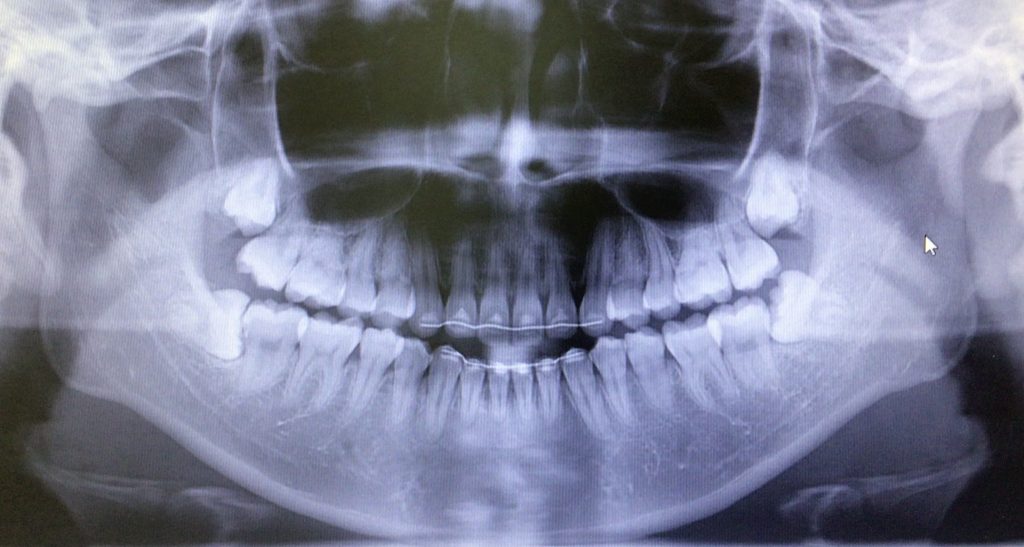

“奥歯の歯ぐきが痛い、腫れた”は親知らずが原因かもしれません

横向きの親知らずは歯磨きがしにくい為、ひとつ前の歯がむし歯になるリスクもあります